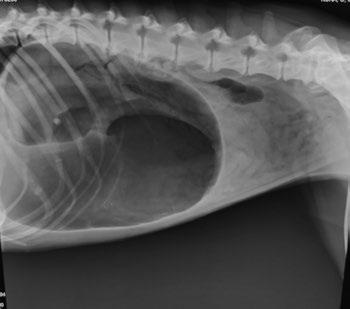

Las proyecciones de tórax incluyen: ventrodorsal, dorsoventral y lateral (figura 1). Es importante extender bien las extremidades anteriores para evitar superposiciones de estructuras. Por norma general, para un buen estudio radiográfico se solicitan tres proyecciones de tórax (LLD, LLI y VD o DV). De este modo podemos evaluar la silueta cardiaca, el estado del pulmón de forma bilateral y la circulación en su totalidad. En algunas patologías como las masas pulmonares, se puede ver esa imagen con claridad en una proyección lateral y en la contraria no verlo por superposición de estructuras. En pacientes con respiración comprometida se debe realizar la proyección que menor dificultad respiratoria le genere, preferiblemente bajo sedación para evitar el estrés, y si se

puede elegir, una proyección dorsoventral o ventrodorsal (figura 2).

Figura 3. Proyección lateral de abdomen. Dilatacióntorsión de estómago. Figura 1. Proyección lateral de tórax. Neumotórax. Figura 2. Proyección ventrodorsal de tórax. Metástasis pulmonar.